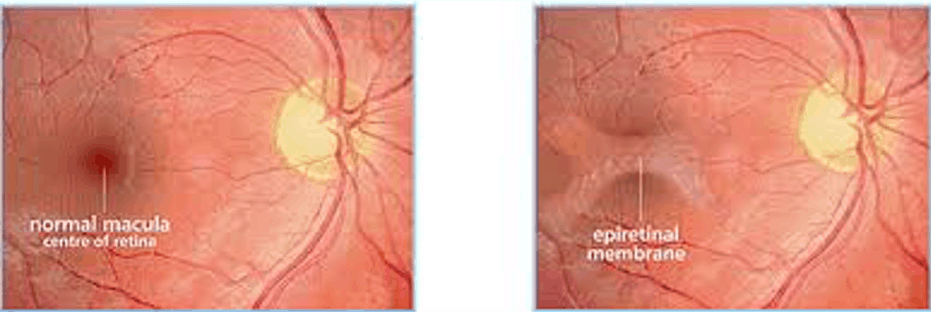

What is an epiretinal membrane?

An epiretinal membrane is a thin sheet of fibrous tissue that develops on the surface of the macular and can cause problems with central vision.

This is because this membrane can contract and cause distortion of the retina. As the macular is responsible for visually demanding tasks such as reading and sharp vision, epiretinal membranes can affect patients quite a lot.

What causes an epiretinal membrane?

Epiretinal membranes can occur from:

- Previous retinal tears or retinal detachment

- Retinal vascular diseases such as: diabetic retinopathy or vein occlusion

- Previous eye surgery

Epiretinal membranes also increase with age. Studies have shown that 2% of those over 50 and 20% over age 70 can have epiretinal membranes, although most do not need treatment.